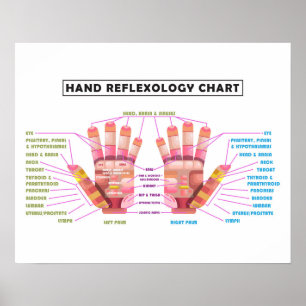

20" x 16", Hand Reflexology Poster

Price$45.35